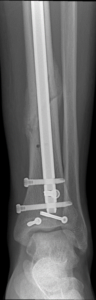

Nonunion and malunion repair related to post-traumatic conditions and/or prior surgery

Acute fracture care of the pelvis and the extremities